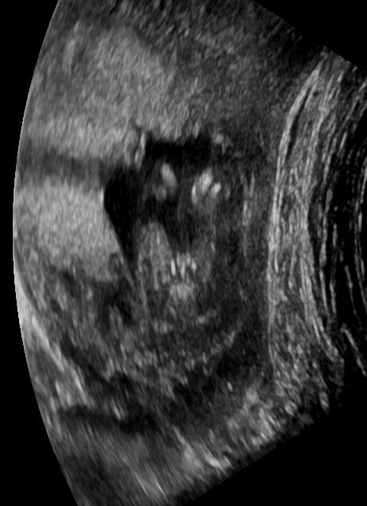

Attachment 42550NIPT said girl & this is from a gender scan at 16 weeks, also said girl. After 4 boys I’m still in shock!! I realise I sound crazy asking but please reassure me. Much appreciated xx